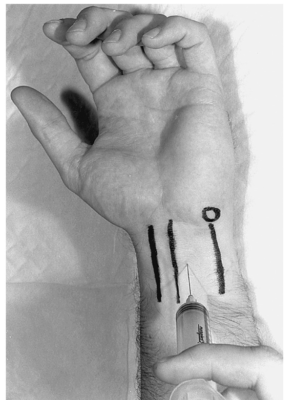

Tiêm corticosteroid (1mL triamcinolone, 40 mg / mL) vào ống cổ tay có thể cải thiện các triệu chứng trên bệnh nhân. Có nhiều kỹ thuật tiêm để tránh tổn thương trực tiếp vào dây thần kinh giữa. Mặc dù hiệu quả chủ yếu là ngắn hạn, tiêm corticosteroid có thể đặc biệt hữu ích để kiểm soát đau và giảm triệu chứng cho những bệnh nhân muốn trì hoãn phẫu thuật.